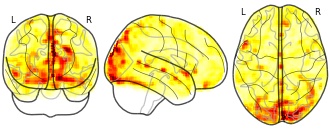

Brain 1 MRI (NIfTI format)

License information was derived automaticallyDescriptionHigh-resolution T1-weighted image of brain1 acquired on a 3T GE Discovery MR 750 system at 0.3mm isotropic voxels.

High-resolution T1-weighted image of brain1 acquired on a 3T GE Discovery MR 750 system at 0.3mm isotropic voxels.